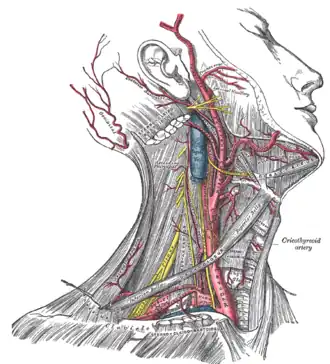

| O nervo frênico e suas relações com outros nervos. | |

O nervo frênico desce obliquamente com a veia jugular interna através do escaleno anterior, para a camada pré-vertebral da fáscia cervical profunda e as artérias cervical transversa e supraescapular. À esquerda, o nervo frênico cruza para a primeira parte da artéria subclávia. À direita, encontra-se na parte anterior do músculo escaleno e cruza para a segunda parte da artéria subclávia. Em ambos os lados, o nervo frênico segue posterior a veia subclávia conforme ela entra no tórax, onde ela segue anterior para a raiz do pulmão e entre o pericárdio fibroso e da face mediastinal da pleura parietal.[1]

Encontrado no meio do mediastino, ambos os nervos frênicos seguem a partir dos nervos C3, C4 e C5 ao longo do músculo escaleno anterior para a bainha carotídea.

- O nervo frênico direito passa sobre a artéria braquiocefálica, posterior à veia subclávia e então atravessa a raiz do pulmão direito anteriormente, em seguida deixando o tórax, passando através da abertura do hiato da veia cava no diafragma no nível de T8. O nervo frênico direito passa sobre o átrio direito.

- O nervo frênico esquerdo passa sobre o pericárdio do ventrículo esquerdo e perfura o diafragma separadamente.

Dissecção do lado direito do pescoço, mostrando as artérias carótida e subclávia.

Dissecção do lado direito do pescoço, mostrando as artérias carótida e subclávia. -